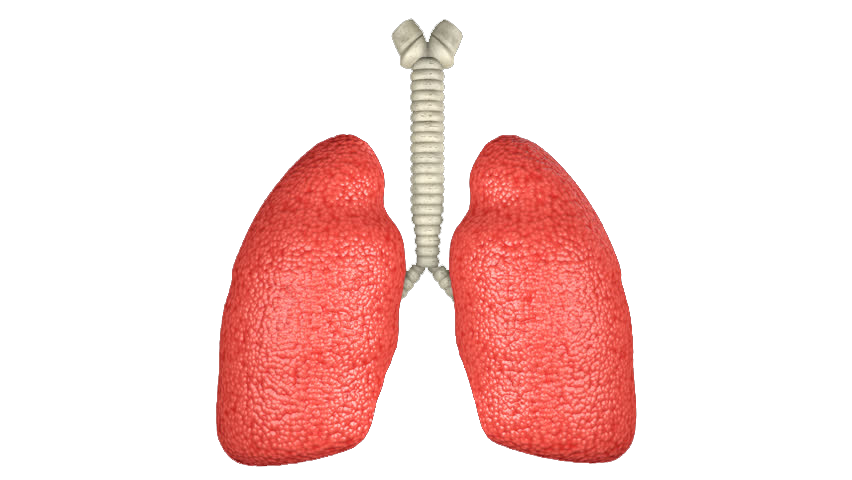

- Sistemi i frymëmarrjes

- Frymëthithja dhe frymënxjerrja

- Duhanpirja dhe shëndeti